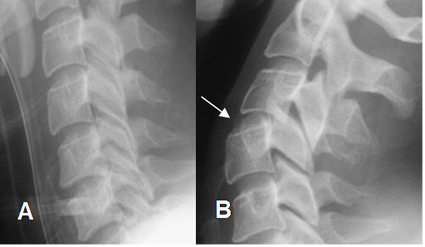

Fig 168. Espasmo muscular.

A: Rx lateral en neutro y B: Rx lateral en flexión. Rectificación de la columna cervical, por espasmo muscular, que impide realizar una adecuada flexión.

Fig 169. Inestabilidad.

A: Rx lateral en neutro. Espasmo muscular, sin signos de desalineación. Se aprecian cambios degenerativos en los espacios inferiores.

B: Rx lateral en flexión. Se logra poca flexión por el espasmo, pero se aprecia leve anterolistesis de C4, sobre C5 y aumento del espacio intervertebral posterior, secundario a lesión ligamentaria.

Fig 170. Inestabilidad.

A: Rx lateral en neutro. Espasmo muscular, sin signos de desalineación.

B: Rx lateral en extensión. Existe retrolistesis de C3 sobre C4, por lesión ligamentaria.